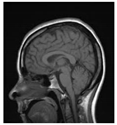

Table 1.

Results of marking and encrypting a medical image.

Table 1 shows the original image, marked image, encrypted image, the decrypted image, and the correlation between extracted blocks and original blocks after decryption using the Double Random Phase Encryption. It is clear that the encryption increases the security, and the mean correlation between the recovered mark and the original mark is measured to be 0.9 in both cases.

The PSNR and SSIM between the original image and marked image are 35.99 db and 0.97, respectively, which means that the marking does not affect the quality of the original image and keeps the invisibility of mark in the image. After encrypting the marked image using the DPRE algorithm, the results show that PSNR and SSIM between the encrypted and marked image are 12 db and 0.1, which verifies the strength of the suggested cryptosystem, as there is no similarity between them. Moreover, the results show that the correlation between the embedded rows and columns with the original is near to 1, verifying the robustness of the mark or signature.